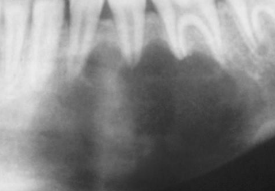

| Periapical(radicular) cysts | Rest of Malassez 被刺激 | - | - | true/ periapical cyst 圓形的光通性包圍根尖 |

牙根吸收, 2cm ↑ 根管治療無效  |

牙根吸收 |